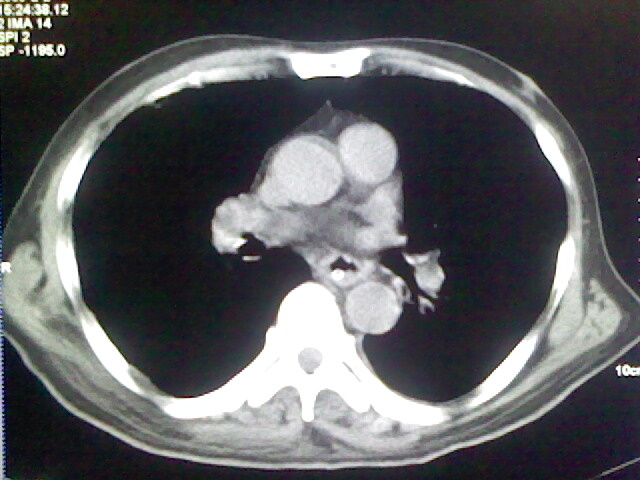

男,70岁,脑出血,长期卧床,左侧背部可触及肿块

右肺病灶考虑炎症性。

慢性间质性炎症,与老年患者长期卧床相关,胸壁软组织及肋骨未见异常。

右肺病灶考虑炎症性

考虑右肺及左肺下叶炎症。

右侧肺部见片状密度增高影,边缘模糊。考虑炎症。另食管壁增厚。

右肺上叶前段病呈楔形,其尖端指向肺门,考虑肺动脉栓塞可能性大.